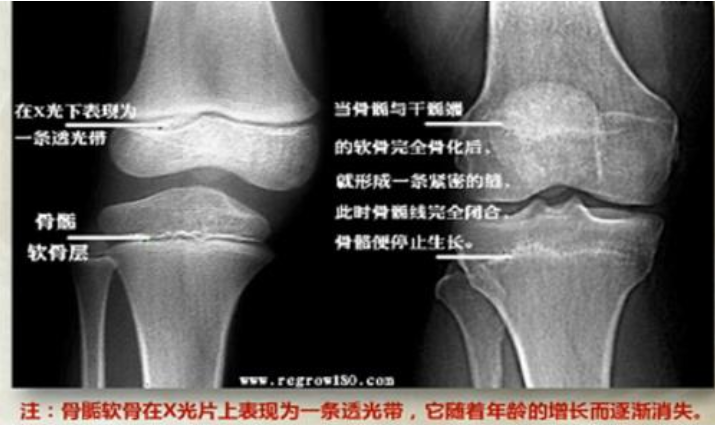

要想知道自己骨骺線處于怎樣的狀態,是否閉合,最好的方法還是到專業的機構進行骨齡檢查。

通過骨齡片,可了解個人的骨骺線閉合情況、身體生長發育潛力,并預測其成年后身高、預判長高空間。

除了通過骨齡片進行專業的預判之外,也可以通過膝蓋骨兩側凹進去的程度來粗略判斷骨骺線是否閉合: